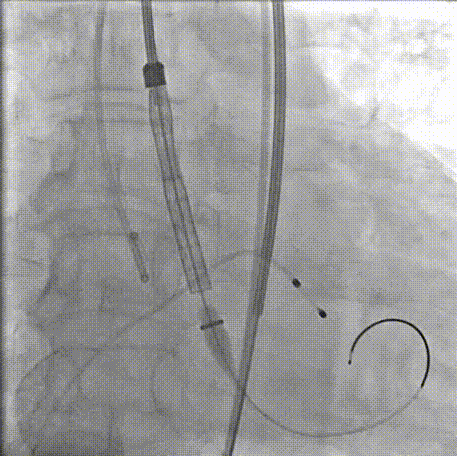

TaurusOne轻松过弓

瓣膜定位

瓣膜释放